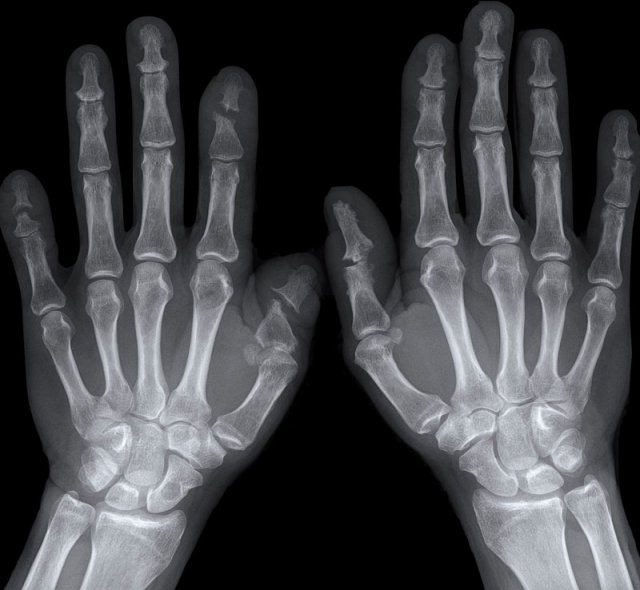

End stage Rheumatoid arthritis. End stage Rheumatoid arthritis.

This is a case with end stage rheumatoid arthritis with severe erosive changes and ligamentous ruptures causing dislocation of the MCP joints.

Scapholunate dissociation (white arrow) is a common finding due to diffuse carpal inflammation. Both the dissociation and inflammation can cause joint space narrowing in the radiocarpal joint.

Notice also the erosion in the distal ulna with surrounding soft tissue swelling (blue arrow).